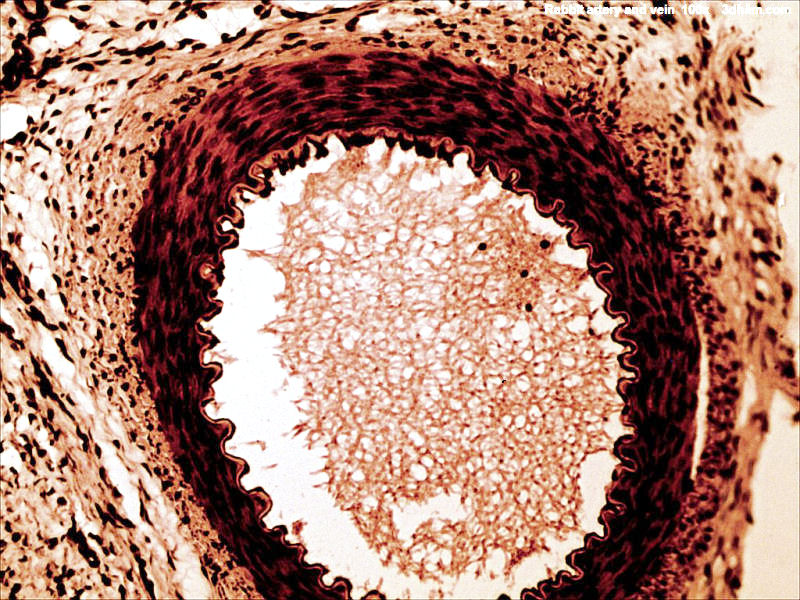

Rabbit artery and vein

Source: http://www.3dham.com/microgallery/ Date: 1 June 2009 Author: John Alan Elson Licence: Creative Commons Attribution-Share Alike 3.0 Unported